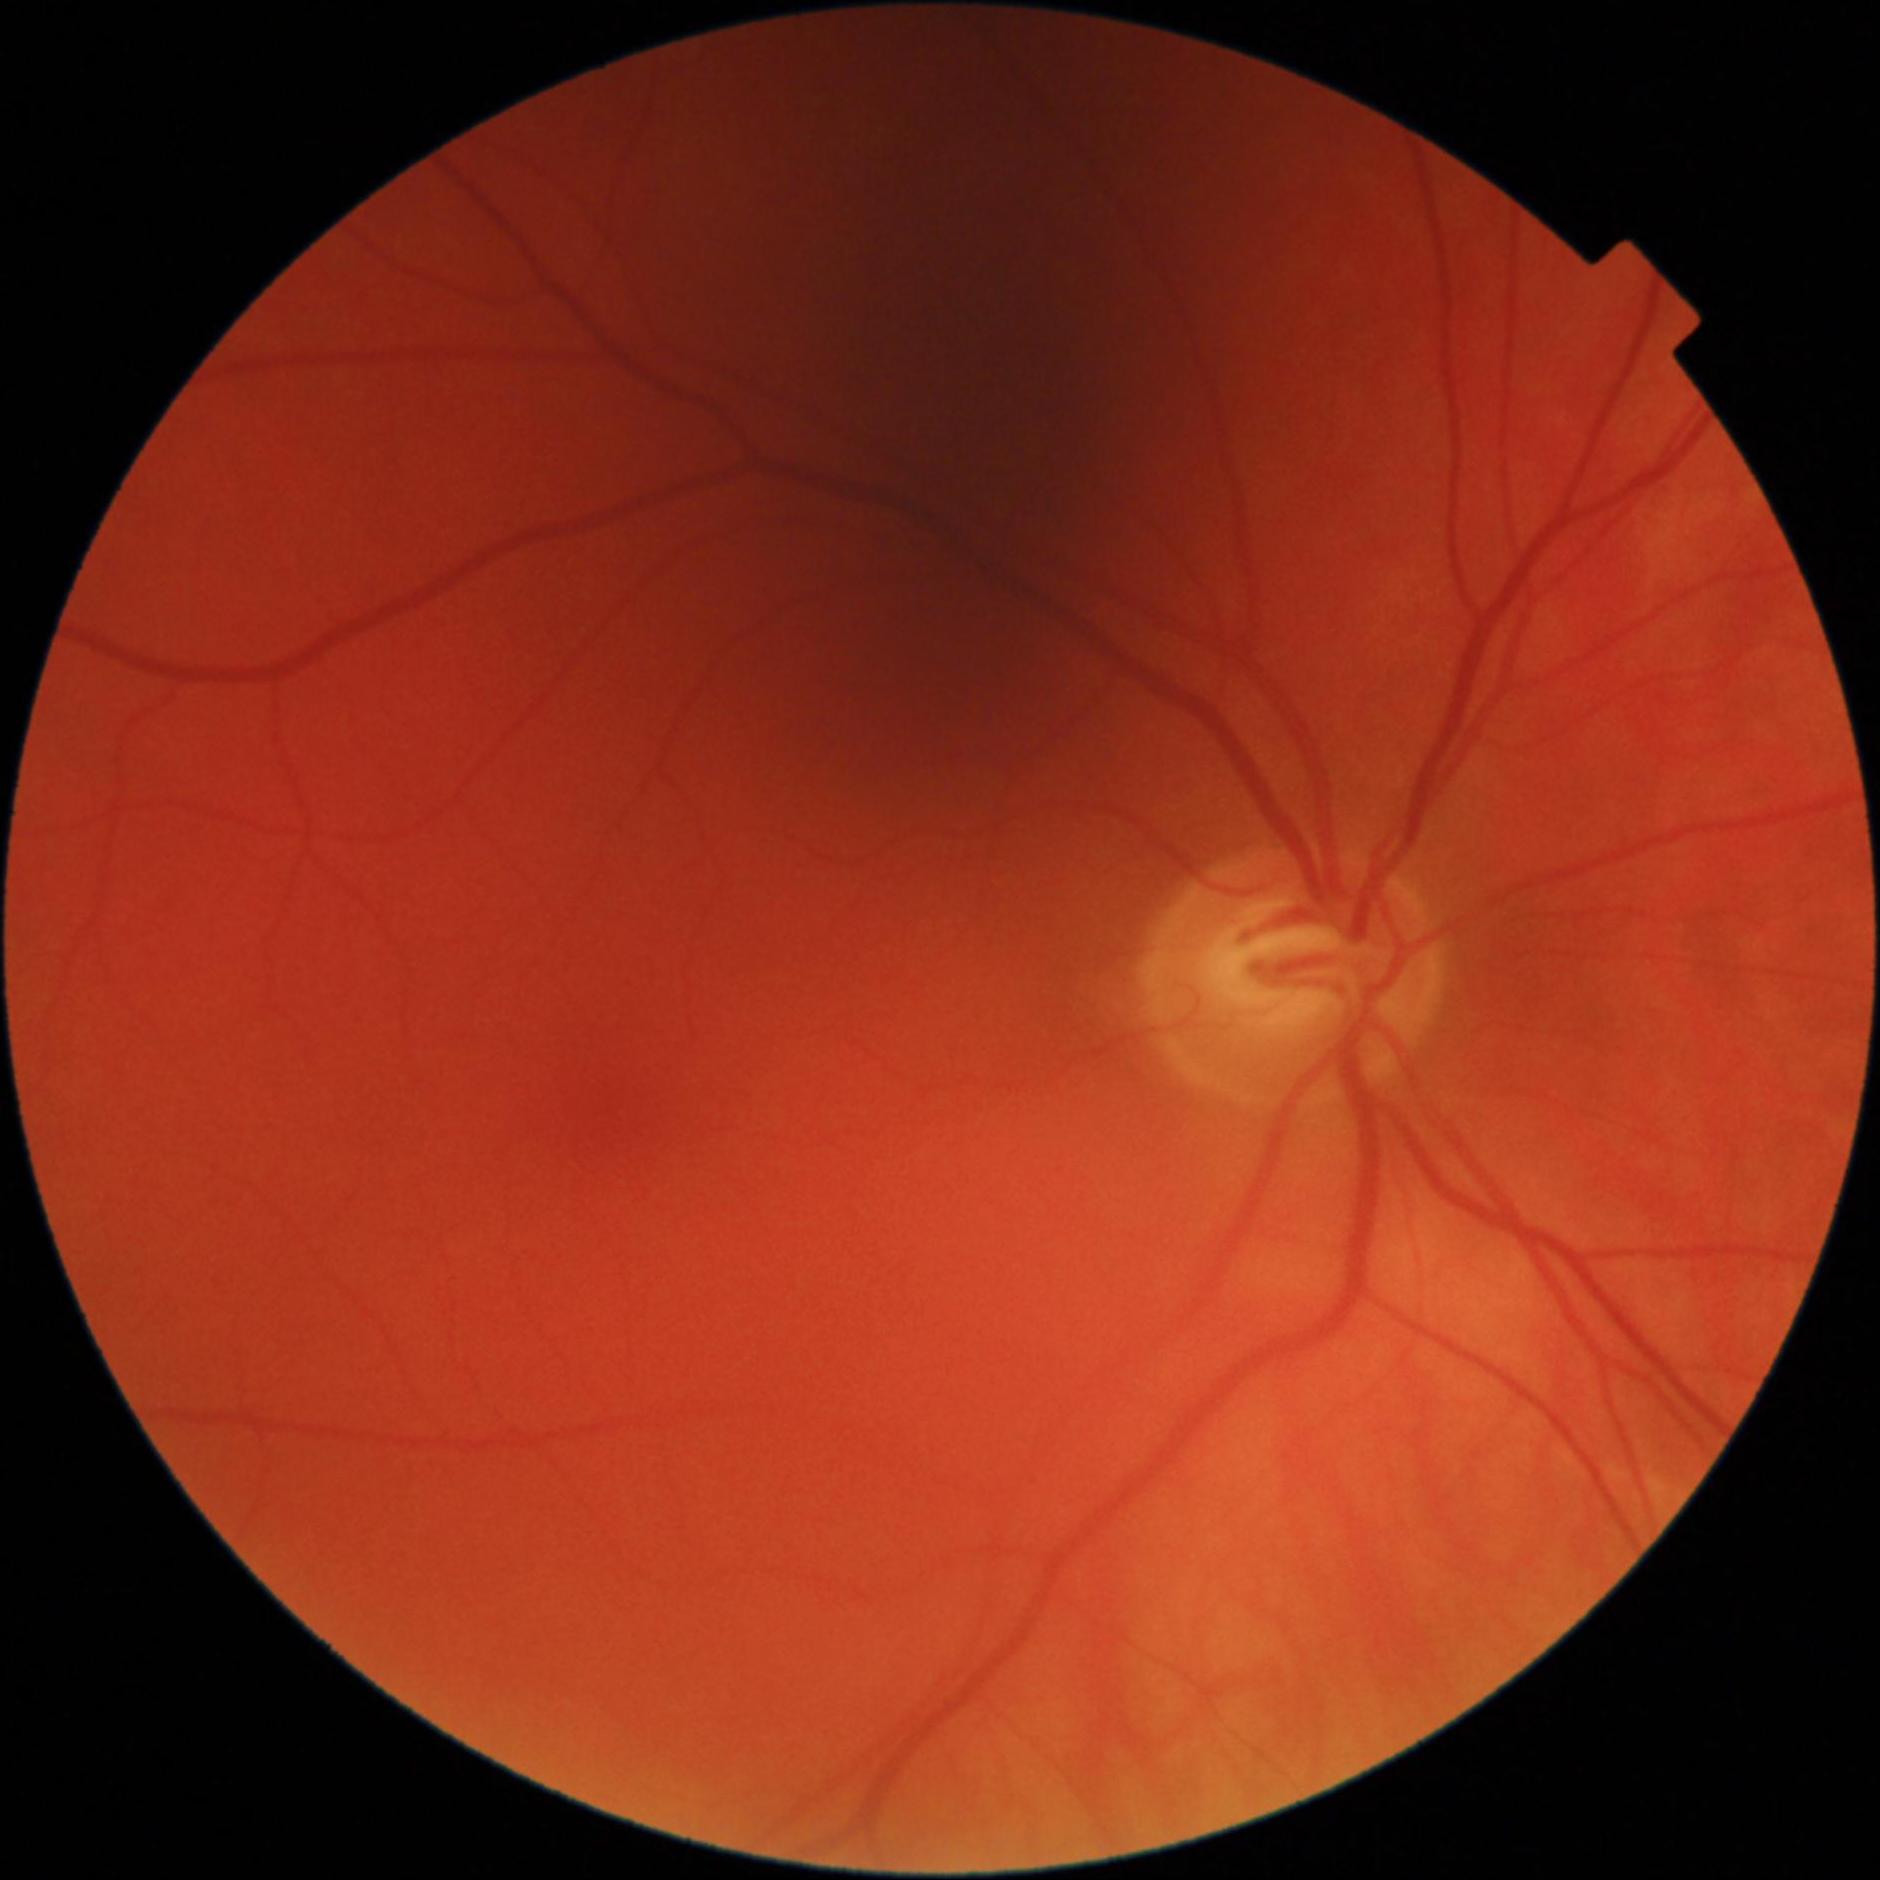

GON is diagnosed through a comprehensive ophthalmic examination that includes intra-ocular pressure (IOP) measurement, anterior chamber and angle assessment, optic disc (OD) inspection, visual field assessment, and optic nerve head imaging [1, 4]. Although effective, these procedures require the expertise of an ophthalmologist and access to specialized, often costly, equipment, which can be a limiting factor. Alternatively, computer-aided analysis of digital fundus images (DFI) can be used to identify GON. DFIs are captured using a fundus camera, which photographs the posterior segment of the eye and provides a clear view of the OD [5].

Recent studies have increasingly utilized deep learning (DL) models for automated GON detection using DFIs [6–8]. However, a major limitation in published research is that GON reference labels are often derived solely from DFI evaluations rather than comprehensive ophthalmic examinations [9–12]. This approach intrinsically reduces the GON detection task to a subjective evaluation of the OD, which has inherent limitations in identifying GON. Consequently, DL models trained exclusively on DFIs may inherit biases, be influenced by subjective interpretations, and inconsistent annotations, include examples that are not verified and potentially diverge from the true clinical manifestation of GON. Additionally, this method can be error prone, since other ophthalmic conditions may mimic the appearance of a GON cupped optic disc, such as ischemic optic neuropathy and compressive optic neuropathy [13].

The Hillel Yaffe Glaucoma Dataset (HYGD) was developed to address this issue, as part of the research study by Abramovich et al. [14]. Unlike most existing datasets, HYGD provides gold-standard GON annotations, where diagnoses are based on a full ophthalmic examination including OCT and VF, rather than subjective DFI-based evaluations. This dataset aims to enhance DL model reliability and reduce biases in automated GON detection.

The dataset was curated by the Hillel Yaffe Ophthalmology Department Glaucoma Unit, Hadera, Israel, between 2022-2024. DFIs were captured using a TOPCON DRI OCT Triton retinal camera with a 45° FOV. The dataset includes subjects aged 36 to 95 years, with 73% of the DFIs classified as glaucomatous. Patient selection followed specific inclusion and exclusion criteria to ensure data quality and clinical relevance.

All DFIs were deidentified, ensuring that any personal identifiers were removed. To maintain consistency, images were cropped to a square format by removing black borders. A quality score for each DFI was computed using FundusQ-Net [5] and is included in the dataset.

HYGD employs gold-standard annotations, meaning that GON labels were assigned based on a full ophthalmic examination, rather than being inferred solely from DFIs.

Patients are diagnosed with GON based on a comprehensive ophthalmic examination, which includes visual acuity (VA) assessment, intraocular pressure (IOP) measurement, anterior and posterior segment evaluation, angle examination using gonioscopy, and posterior pole assessment using a 78-diopter lens while the pupil is dilated. Additionally, OCT is performed to assess the retinal nerve fiber layer (RNFL) and macula. Visual field tests, specifically the 24-2 and 10-2 tests, are conducted prior to diagnosis. Furthermore, all patients are followed up for at least a year to monitor the disease's progression and validate the labeling accuracy. All examinations were carried out by professional glaucoma specialists, while the images and visual field tests were handled by trained technicians.